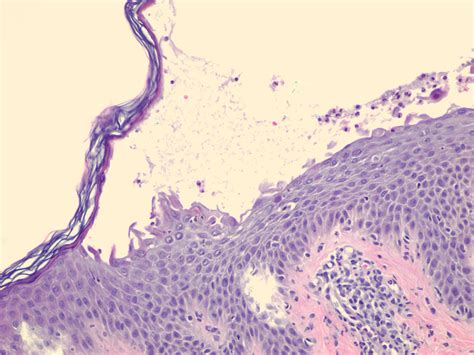

Visual aids can be incredibly helpful in understanding the severity and characteristics of SSS. Below are some descriptions of what you might see in Scalded Skin Syndrome Pictures:

1. Early Stage: The skin may appear red and tender, with small blisters forming. The affected areas may look like a mild sunburn or rash.

2. Progressive Stage: As the condition progresses, the blisters become larger and more numerous. The skin may start to peel in sheets, revealing the underlying tissue.

3. Advanced Stage: In severe cases, large areas of the skin may peel off, leaving the body vulnerable to further infection. The skin may appear scalded or burned, hence the name "scalded skin syndrome."

4. Healing Stage: With proper treatment, the skin begins to heal. New skin cells form, and the affected areas gradually regain their normal appearance.

While visual aids are helpful, it is important to consult a healthcare professional for an accurate diagnosis and treatment plan.